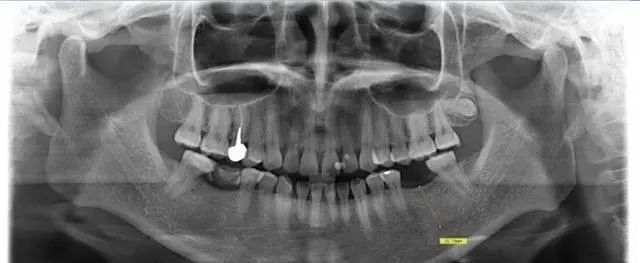

我们看第一张全景片

患者的下颌有一颗牙齿缺失,需要进行种植牙手术,手术前对患者的口腔进行了全景片的拍摄。并从软件中测量患者缺失牙位的可用骨高度为20.75mm。看到这个数值,如果是有经验的种植医生肯定会第一时间怀疑机器的放大率,因为通常牙齿缺失后,牙槽骨都会吸收,而尤其是牙齿缺失比较久的患者,牙槽骨的条件都不是很理想。可以说能够拥有20.75mm这么高的牙槽骨几乎是不现实的。